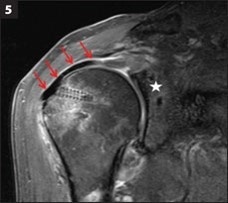

MRI 6 Months After SCR